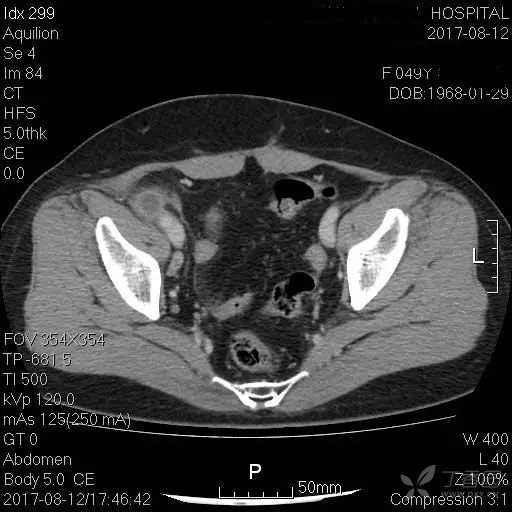

急性阑尾炎ct诊断鉴别诊断

图片尺寸1080x810